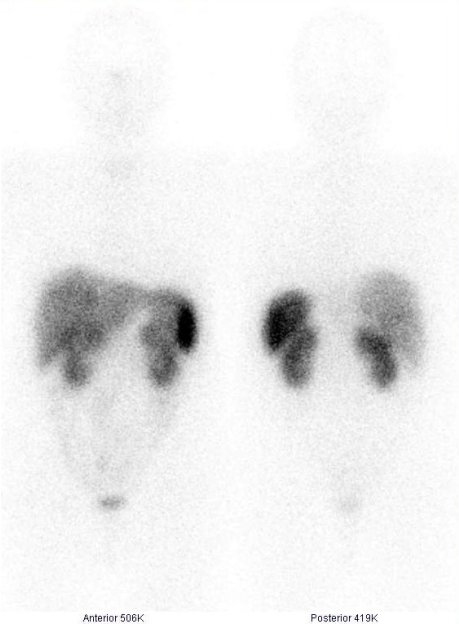

/ Obr. č. 1: Celotělová scintigrafie v přední a zadní projekci 4 hod. po aplikaci OctreoScanu /

Je patrná fyziologická difuzní depozice radioaktivity v játrech, slezině, v ledvinách a močovém měchýři, nepatrně ve střevech. Scintigraficky již jaterní ložisko neprokazujeme, je patrné pouze na CT jako hypodenzní ložisko v horní části jater na pomezí laloků. Nález tedy svědčí pro regresi nádorového ložiska karcinoidu v játrech – léze již není viabilní a jedná se o ložisko nekrotické po provedené chemoembolizaci.

/ Obr. č. 4: Celotělová scintigrafie v přední a zadní projekci 24 hod. po aplikaci OctreoScanu. /